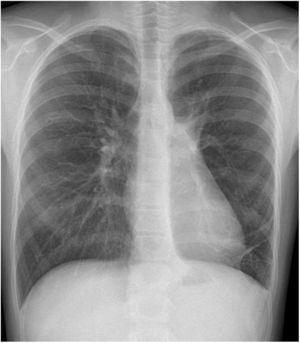

Paciente de 10 años que acude derivada a consulta de neumología tras detección casual de hipoventilación global a nivel del hemitórax izquierdo en el contexto de un cuadro de gastroenteritis. Se trataba de una niña sana, sin antecedentes de interés. Se realiza radiografía de tórax y angio-TC torácico donde se objetiva una importante hiperinsuflación del hemitórax izquierdo (fig. 1). Se lleva a cabo broncoscopia con evidencia de estenosis bronquial por compresión extrínseca. Ante el tamaño de la lesión con desviación mediastínica se decide realización de lobectomía inferior izquierda. El informe anatomopatológico fue compatible con malformación congénita de la vía aérea pulmonar (MCVAP) tipo 4. En el postoperatorio se detecta hipoventilación basal con hidroneumotórax izquierdo en radiografía de tórax (fig. 2) que precisó drenaje. Desde entonces presenta buena evolución clínica, asintomática desde el punto de vista respiratorio con resolución ad integrum (fig. 3).